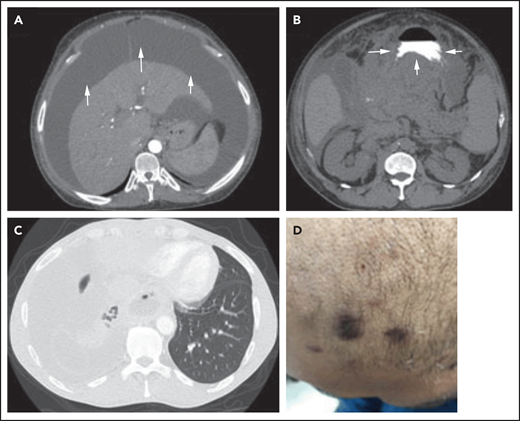

PEL/EC-PEL cells are large and pleomorphic with immunoblastic/plasmablastic features. Cells that are Reed-Sternberg–like or anaplastic large-cell lymphoma-like are often seen (Figure 3A). By definition, PEL/EC-PEL is KSHV+ and uniformly expresses LANA (Figure 3A).3,60,62,71,75,77

Histopathology of PEL and MCD. (A) PEL cells are large, with pleomorphic immunoblastic/plasmablastic features. A mitotic figure indicates proliferation of the tumor cells. Immunostaining of a cytospin preparation (insert) with an antibody to LANA shows the characteristic dot pattern in the nucleus (modified Giemsa stain, ×100 original magnification; insert: immunoperoxidase, ×100 original magnification). (B) Follicles in KSHV+ MCD are often involuted and hyalinized. There are many plasma cells in the interfollicular area and prominent vascular proliferation. In addition, a number of KSHV+ plasmablasts (arrows; insert) are present in mantle cell zones. These plasmablasts are LANA+ and vIL-6+ (hematoxylin and eosin [H&E] and immunoperoxidase staining, ×20 original magnification; inserts: ×60 original magnification).

KSHV-MCD lymph nodes show morphologic and immunophenotypic features similar to those of other types of CD. However, some KSHV-MCD lymph nodes may show features that overlap with those seen in HIV-related benign lymphadenopathy. Overall, the architecture of the lymph node is preserved with patent sinuses. There is usually prominent vascular proliferation in the interfollicular areas with significant numbers of plasma cells, which are polytypic by immunostaining. There may be a decreased number of interfollicular lymphocytes, particularly in HIV+ patients. The follicles are variably involuted and hyalinized. In some cases, there is a mixture of hyperplastic and involuted follicles. Prominent vessels penetrating follicles can be seen. The mantle cell zones may be pronounced, and the border between the mantle zone and the interfollicular area can be blurred.38,108-112

In contrast to other types of CD, medium to large relatively round mononuclear cells are seen (Figure 3B), which are the KSHV-infected cells first described as plasmablasts in 2000.109 Although this is likely a misnomer, KSHV+ cells in this disease have some features reminiscent of plasma cells, such as cytoplasmic immunoglobulin expression, MUM1 positivity, and relatively abundant cytoplasm. However, they differ from plasma cells in that they express B-cell antigens and are usually CD138−. These cells are preferentially seen in mantle cell zones and/or abutting germinal centers. Plasmablasts are positive for LANA; many also express cytoplasmic vIL-6 (Figure 3B). Expression of other KSHV lytic proteins by plasmablasts, including ORF59 and K8, has also been described. Plasmablasts are B cells that exhibit variable, often faint to negative, expression of CD20, CD79a, and PAX5 and lack expression of CD10 and BCL6, but they are uniformly positive for IRF4 and BLIMP1. Thus, these cells express markers of terminal B-cell differentiation. The cells are typically CD30− and CD138− but are usually CD38+.38,109,113-115 Plasmablasts also express the B-cell transcription factor OCT2, important for immunoglobulin expression. There is monotypic expression of immunoglobulin Mλ in LANA+ cells, with only a few random cytoplasmic κ+ cells seen in some cases. This latter finding may be due to the ability of KSHV to induce B-cell receptor revision via reinduction of Rag-mediated V(D)J recombination, with eventual switch from κ to λ light chain expression.116 KSHV+ plasmablasts are only rarely positive for EBV but show a high proliferation rate based on immunostaining for Ki67.38,77,109,110,112,113,115,117,118 The number of KSHV+ cells in a given case is variable, and in some cases, large aggregates of plasmablasts, previously known as microlymphomas, are seen. Molecular studies have found that most if not all cases of KSHV-MCD contain polyclonal or oligoclonal B cells, including cases with plasmablast aggregates. In addition, the cells comprising the plasmablast aggregates have unmutated immunoglobulin genes, indicating that they did not traverse the germinal center.115,119